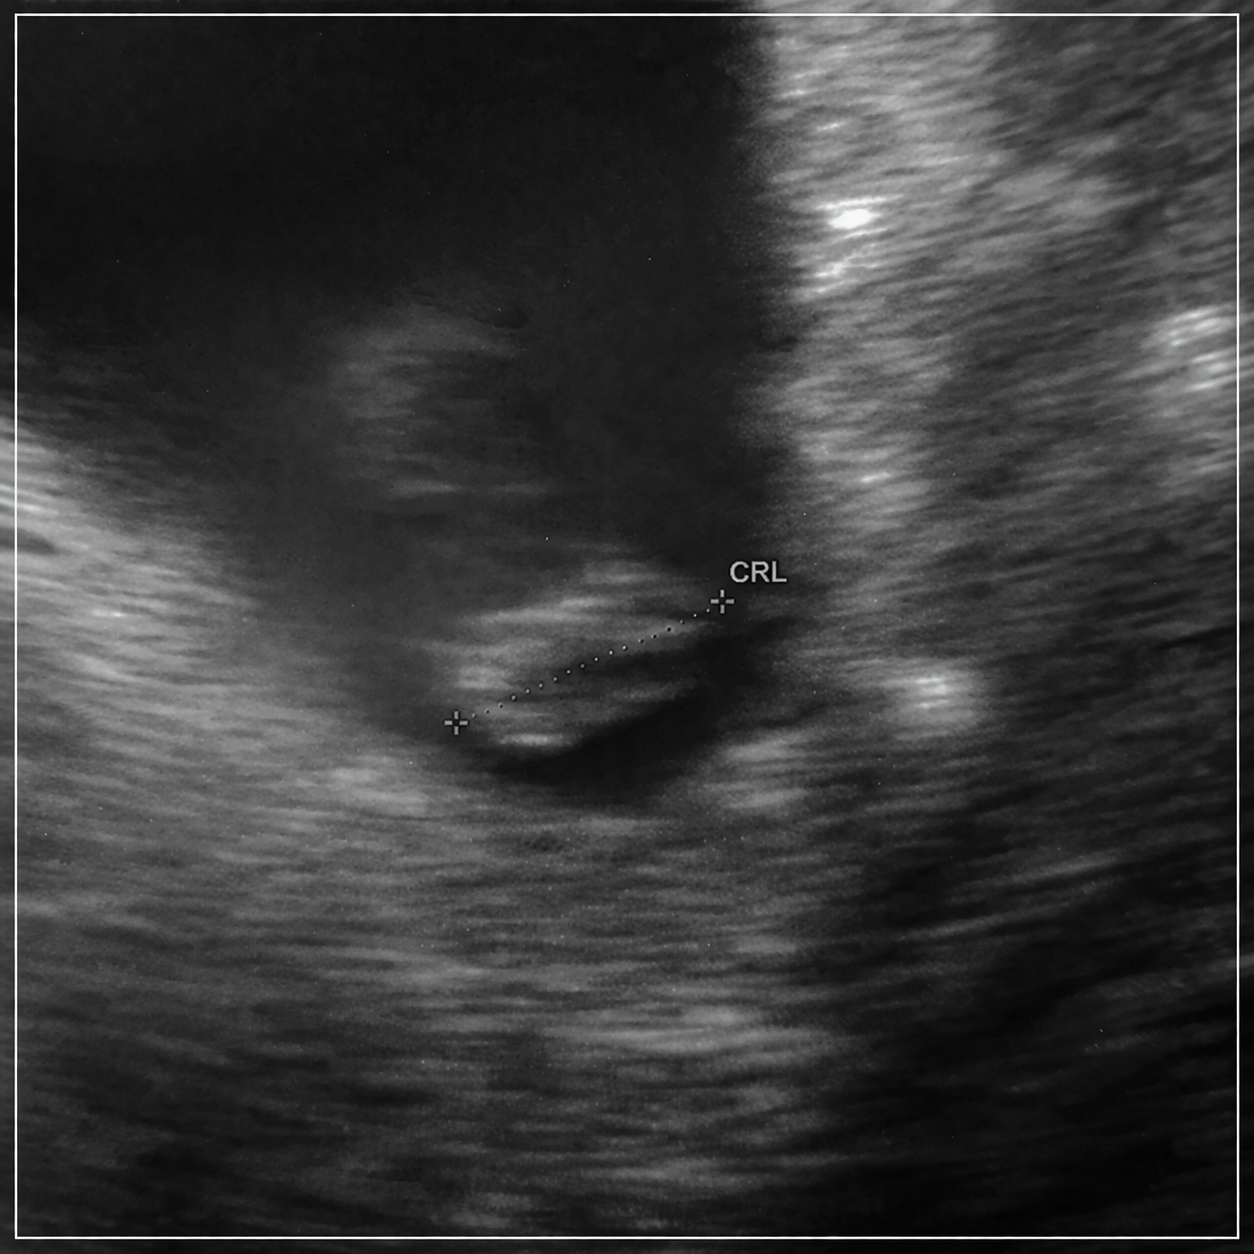

A z dobrych wiadomości moja kropeczka ma już rączki i nimi ruszała na USG i ma już 2cmNawet było widać długą i gruba pępowinę

Jaka idealna fasolkaSynek 39 stopni,dostał już antybiotyk